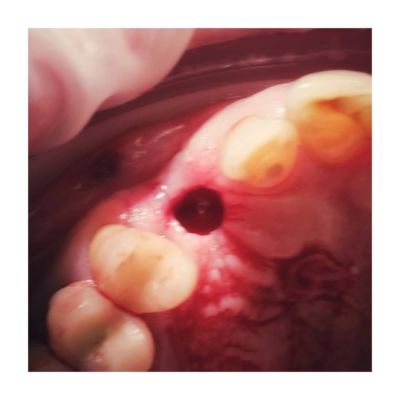

Po około 3 - 6 miesiącach - pacjent zostaje znieczulony nasiękowo (miejscowo). Lekarz za pomocą specjalnego szablonu ustala miejsce wszczepionego wcześniej implantu.

Wykonywane jest nacięcie i wycięcie dziąsła wokół implantu – tzw. odsłonięcie implantu (jeśli zastosowano gojenie zamknięte). Następuje odkręcenie śruby zamykającej i założenie śruby gojącej pomagającej w wygojeniu dziąsła wokół implantu.